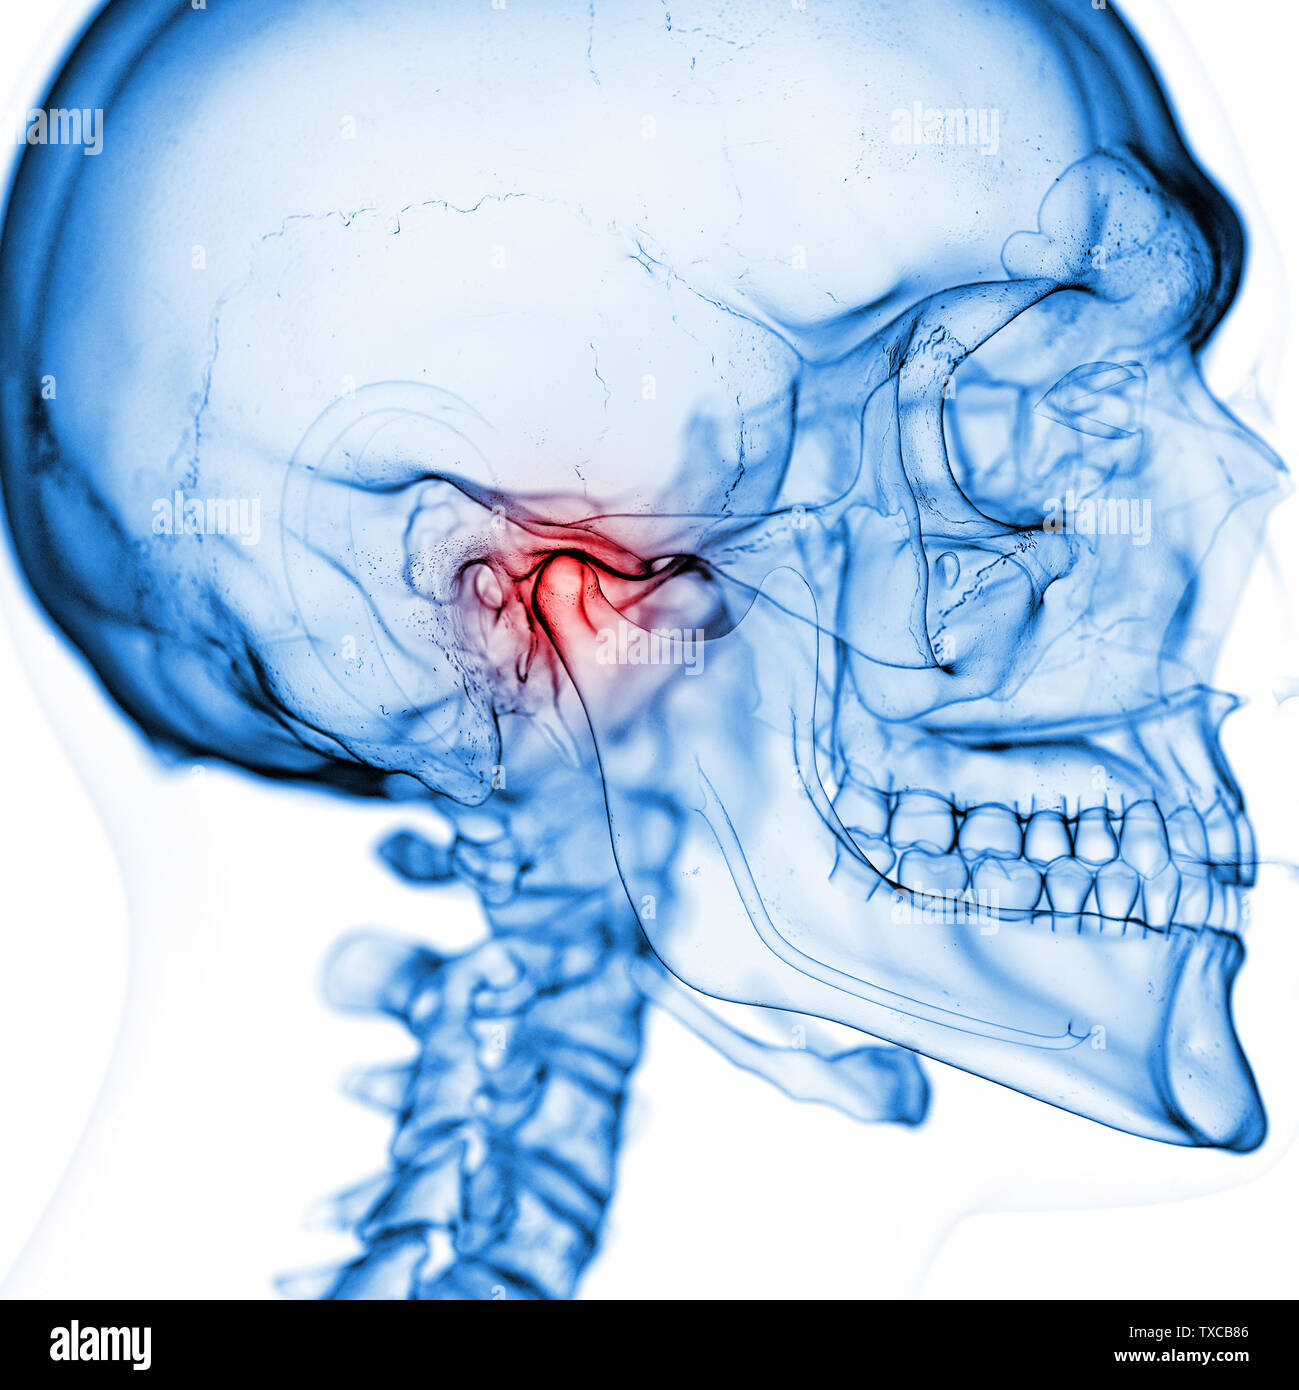

Temporomandibular Joint